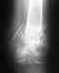

Re: Перелом пяточной кости обеих ног

Уточните пожалуйста срок после травмы, переломы закрытые или открытые, наличие инфицированных ран обл.переломов,как лечитесь?